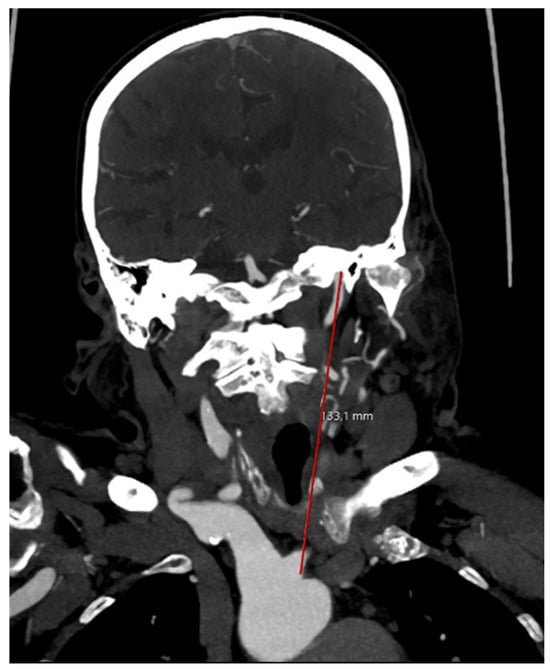

2.2. Arterial Tortuosity Measurement and Definition